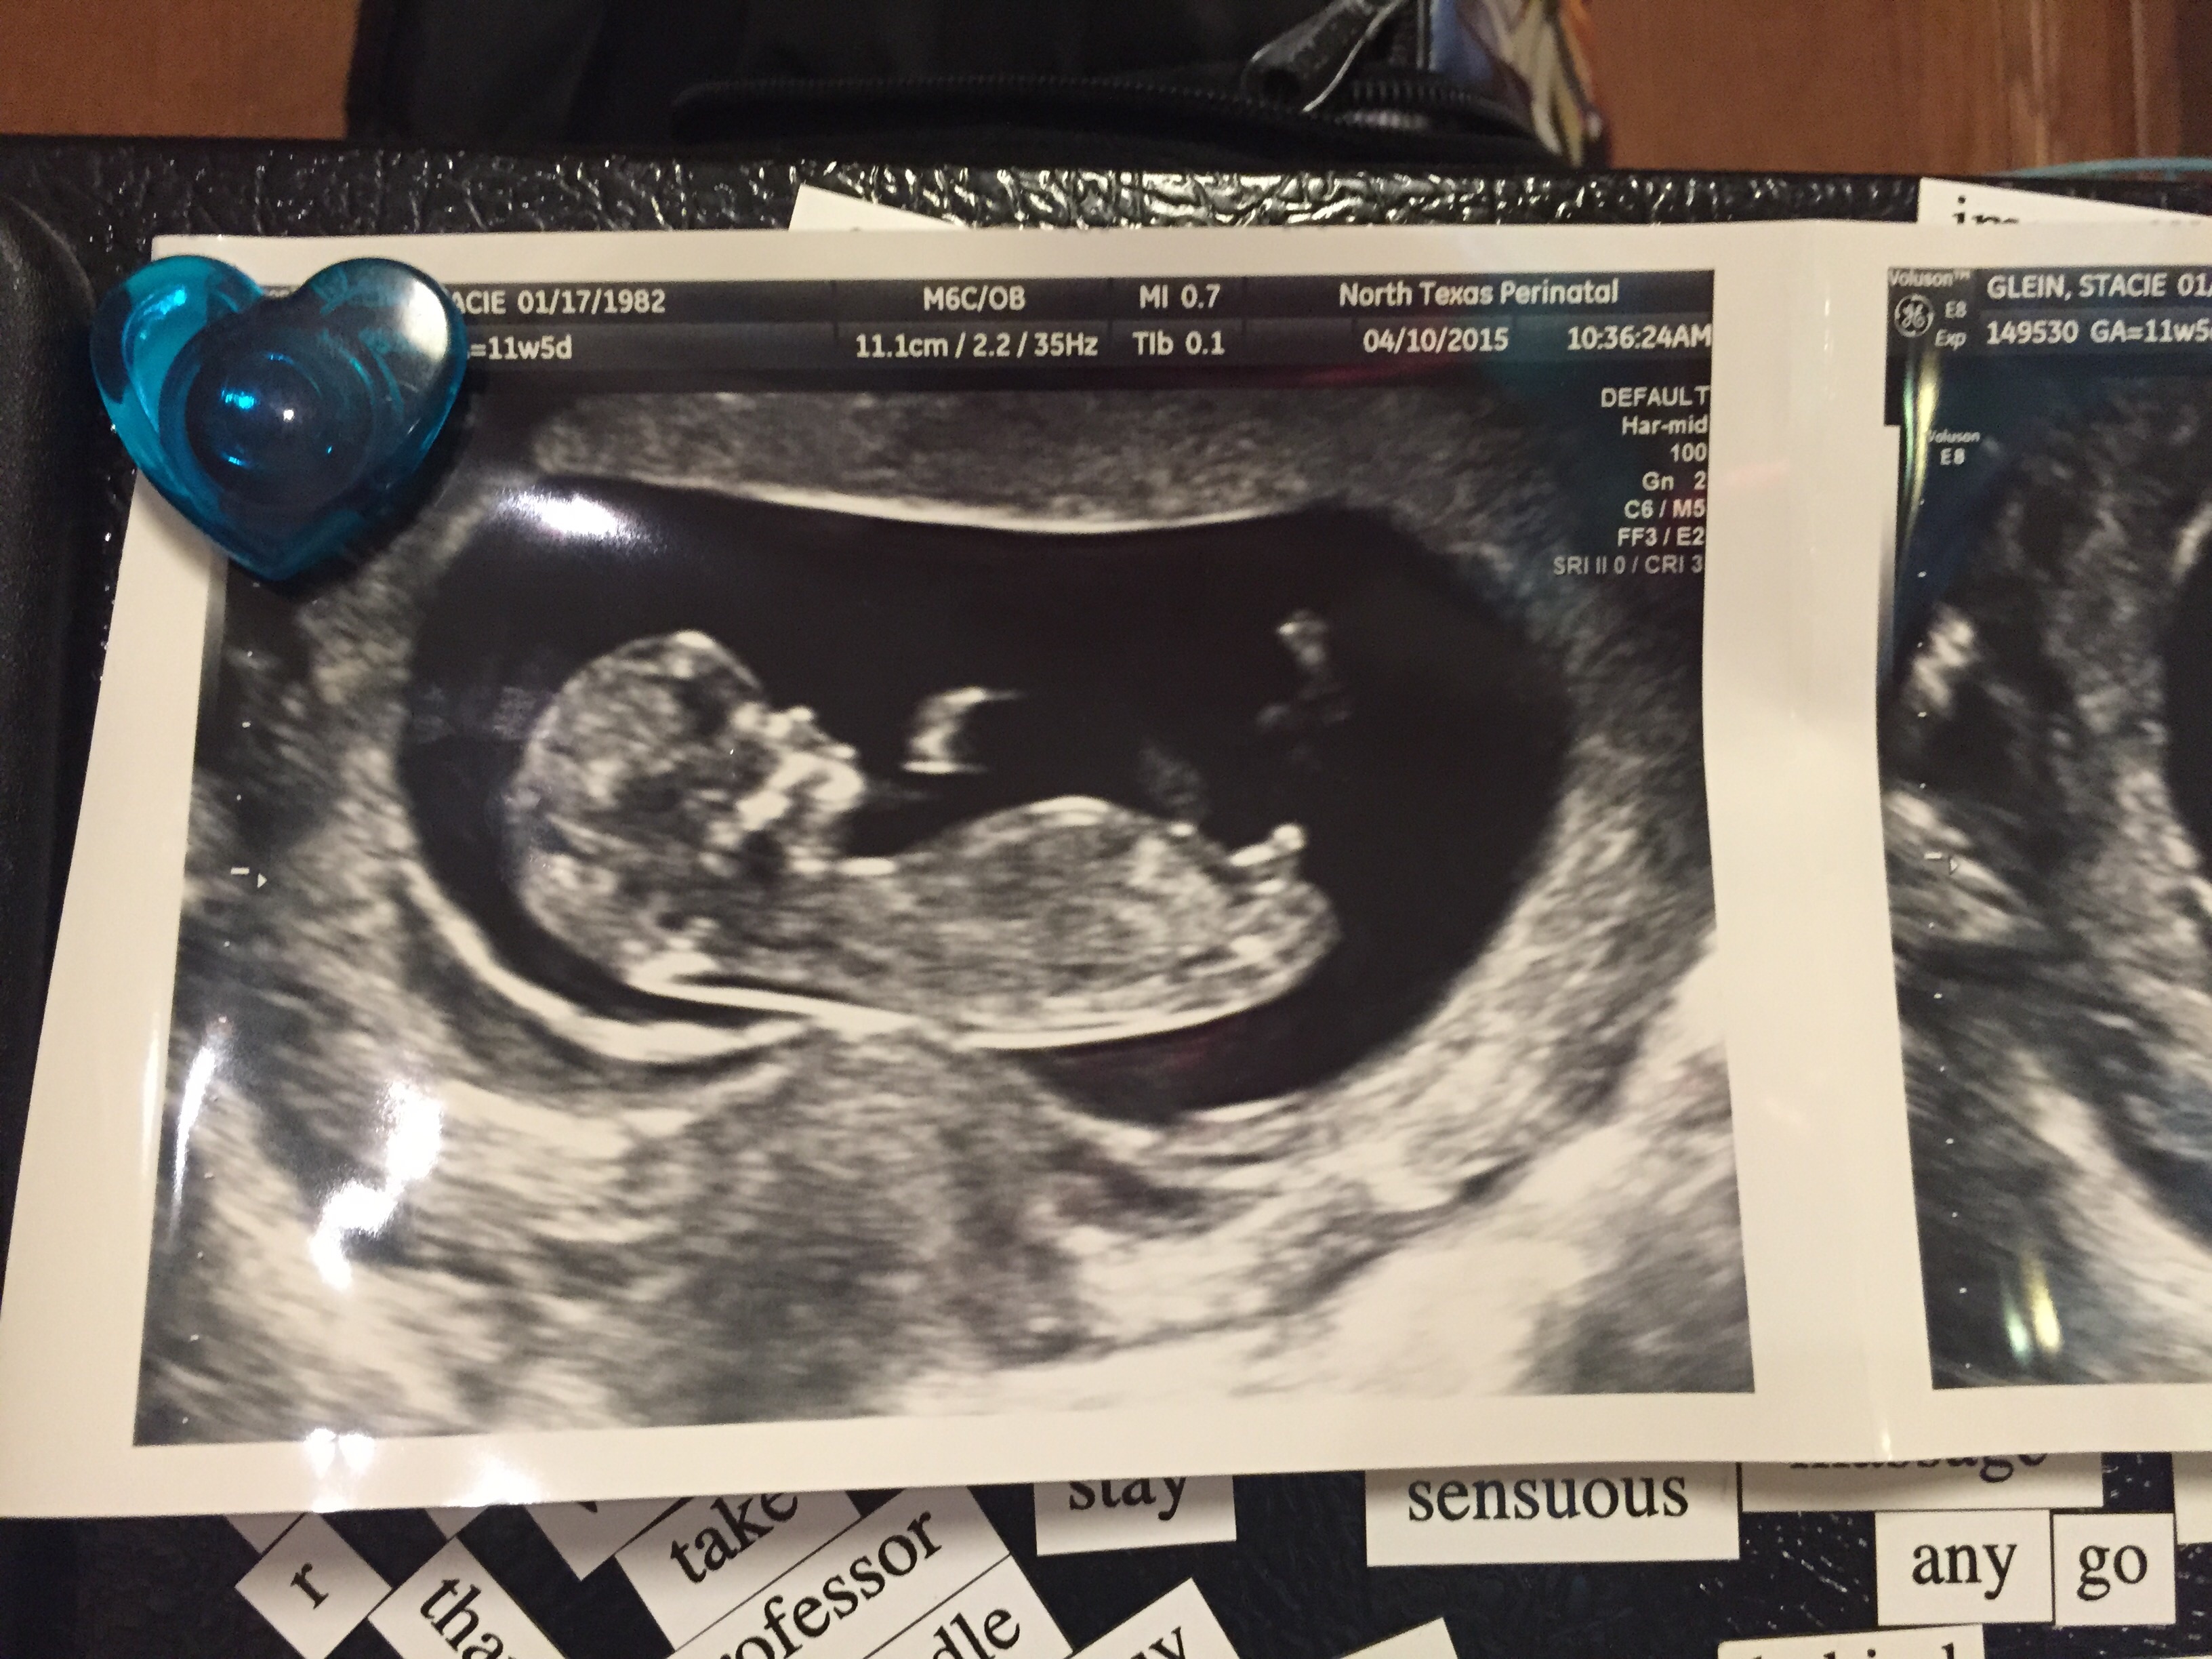

Here's our little love at 12 weeks! I can't get over how much he/she already looks like a 'real' person, can't wait for the next US when we find out the sex! So excited

We also graduated up one whole day! 12w 1d today.